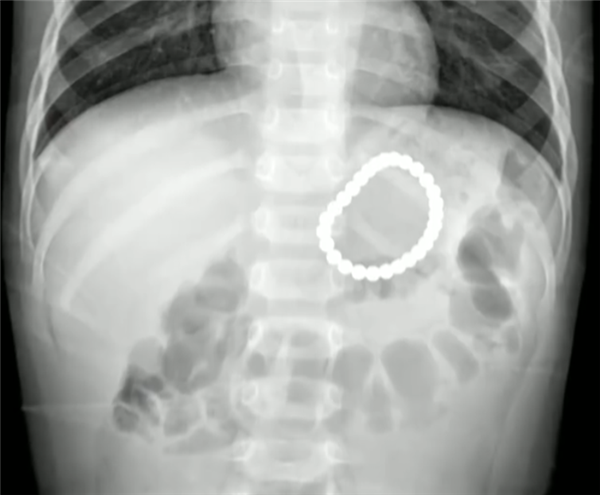

據了解,日前,山東聊城一名2歲大的幼童在玩耍時,就誤吞了28顆5毫米大的磁力珠,送到醫院時已超過20個小時,險些造成胃腸穿孔。

醫生趕緊為這名幼童安排了胃鏡手術,幸運的是,這28顆磁力珠被幼童吞咽后沒有分離,除了部分胃黏膜損傷外,沒有出現其他被夾住、穿孔等情況。